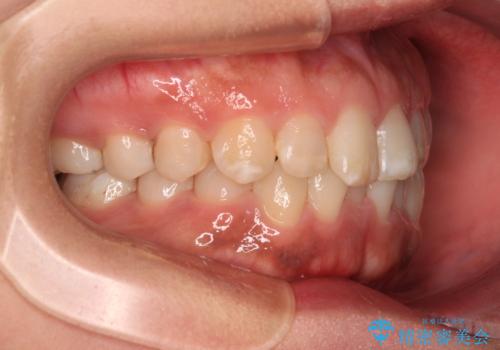

- 上下前歯の叢生を気にして来院された患者様です。

軽度な叢生であり、安価で短期間の治療を規模されていたため、インビザライン・モデレートを用いて矯正治療を行うこととしました。